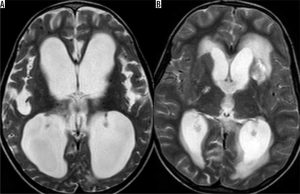

Não úng thủy (Hydrocephalus) là biến chứng thường gặp nhất của bệnh lao ở hệ thần kinh trung ương. Não úng thủy có thể là thông thương hoặc không thông thương. Não úng thủy thông thương (Communicating hydrocephalus) thường gặp hơn và xảy ra do tắc nghẽn dòng chảy dịch não tủy trong các bể nền sọ do dịch tiết của viêm (Hình 8). Ở giai đoạn sau, não úng thủy có thể có là di chứng thứ phát do tình trạng dính sau viêm ở bể nền sọ. Não úng thủy không thông thương (Non-communicating hydrocephalus), mặc dù thường gặp hơn do hiệu ứng khối chèn ép thứ phát do u lao hoặc áp xe não do lao, cũng có thể xảy ra trong các trường hợp phức tạp do viêm não thất (ventriculitis) và viêm màng não thất (ependymitis), có thể tạo ra dịch tiết viêm (inflammatory exudates) và dính sau viêm gây tắc nghẽn, thường ở ngang mức cống não Sylvius.

Hình 8. Biến chứng của viêm màng não do lao. Hình A (T2W axial) biểu hiện giãn lớn não thất bên hai bên cho thấy não úng thủy. Hình B (T2W axial) cho thấy nhiều ổ nhồi máu não ở vùng hạch nền và bao trong (gangliocapsular regions) hai bên.